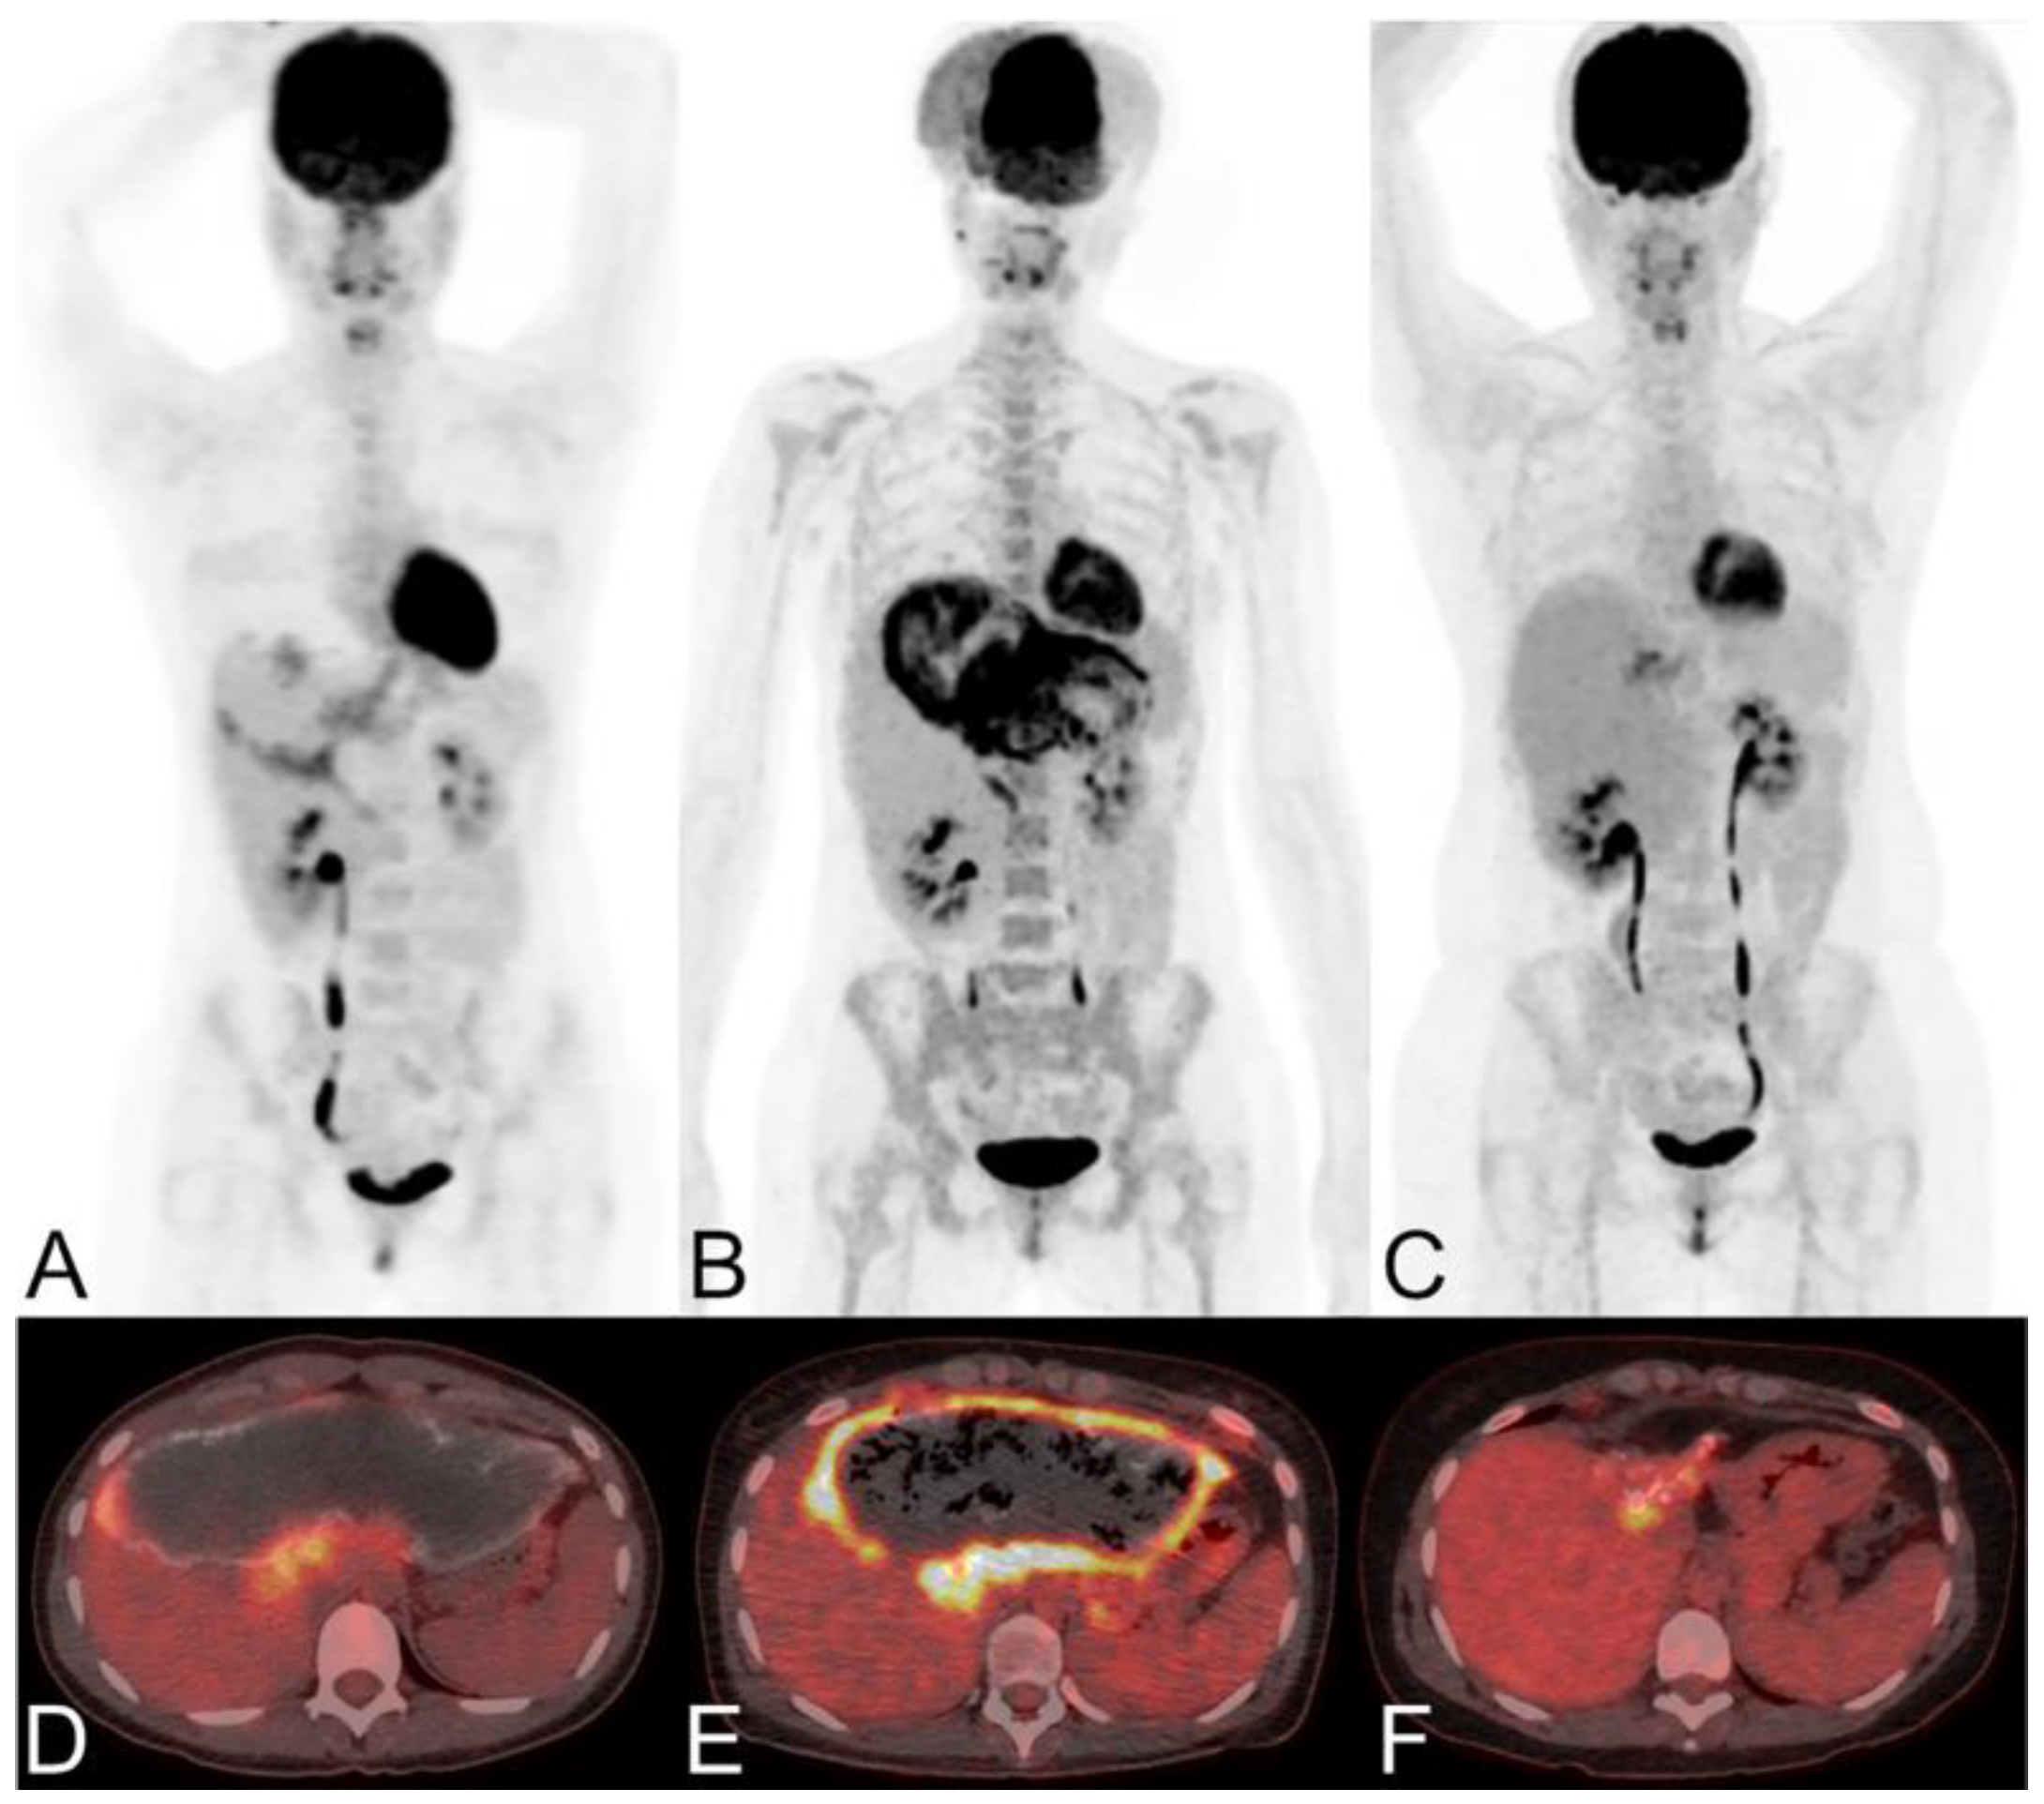

Glucose is the primary energy substrate for parasites and fluorodeoxyglucose positron emission tomography (FDG-PET) has been the gold standard for assessment of the metacestode activity status, which is essential for the individual treatment strategy of the AE patient [104,153,154]. FDG-PET was introduced 25 years ago to monitor the progression of AE lesions. Positive FDG uptake indicates active lesions, while negative FDG uptake suggests parasite abortion, an indication of albendazole withdrawal [155]. This method has proven to be effective, but there are cases of recurrence after discontinuation of medication in some patients [156]. Currently, the improved PET imaging protocol requires both the 3 h post-FDG injection delayed image and the 1 h post-injection image to be negative in order to determine that the result is negative [153]. Delayed imaging can reduce false negatives and enhance the sensitivity in determining the metabolic activity of AE (Figure 8).

As shown in Figure 9, in vitro experiments have demonstrated that immune cells surrounding the AE lesions exhibit high uptake of FDG, whereas parasitic cells within the cysts show low uptake of FDG [157,158,159,160]. Therefore, FDG-PET can indirectly assess parasite activity by monitoring the activity of host immune cells [161]. The metabolic hyperactivity of AE liver lesions on FDG-PET/CT is strongly correlated to the presence of microcalcifications on CT but not with the presence of macrocalcifications [84]. The absence of microcysts on MRI is closely associated with metabolically inactive diseases [138].

Graeter et al. [124] firstly correlated the standardized uptake value (SUV) of HAE on FDG-PET with the morphological features and EMUC-CT classifications of the lesions. Their results show that the SUVs were increased for lesions with EMUC-CT types I–IV primary morphology, compared to the surrounding healthy liver tissue (SUV = 2.5 ± 0.4; p < 0.05). The SUVs of Types I and III were the highest, while those of Type IV were the lowest. Type IV had the highest rate of negative FDG-PET findings, with statistically significant differences compared to the other types, indicating that these SUVs might reflect different stages of the disease. Due to the small number of cases, it was not possible to evaluate Type V lesions. Furthermore, the FDG uptake differed significantly between cases with positive and negative Em2+ serology, in which Type IV lesions are typically associated with negative Em2+ serology. The metabolic rate of FDG images generated with traditional and relative Patlak analysis demonstrates superior performance in visualizing HAE compared to static SUV images [163]. Ozmen et al. [164] retrospectively analyzed 36 patients with pulmonary hydatid disease who underwent FDG-PET/CT imaging, examining lesion characteristics, SUVmax and HUmean values, and lymphatic FDG uptake to assess disease complexity. Their study found that higher SUVmax values may indicate complicated pulmonary hydatid disease, and FDG-PET can aid in prioritizing surgical intervention and evaluating treatment response. For advanced HAE cases where radical hepatectomy is not feasible, autologous liver transplantation (ALT) has emerged as an effective treatment option in recent years. However, various factors post-ALT can readily lead to recurrence and distant metastasis of HAE. 18F-FDG PET/CT is considered to play a crucial role in assisting early detection and assessment of liver function status post-ALT, as well as in evaluating the risk of recurrence or metastasis [165]. Aini et al. [166] use PET/CT and multi-site sampling methods to quantitatively evaluate the range and metabolic activity of HAE lesion microenvironment and connect it with immunological and pathophysiological changes, providing a reference for surgical resection of the lesions and more accurate sample acquisition.

FDG-PET is also used for long-term follow-up of AE (Figure 10). The absence of metabolic activity indicates suppression of parasite activity, which is not equivalent to parasite death. This suppression can persist for several years, and oral medication therapy should be reinitiated when recurrence is detected by PET [167,168,169]. In a retrospective study of 179 AE patients who underwent PET/CT scans, it was found that as the clinical status progressed, significant changes occurred in total immunoglobulin E (IgE), parasite-specific IgE, and serological status (using crude antigen preparations or recombinant/purified antigens such as EM10, Em18, and Em2) [170]. Notably, these serological biomarkers were also significantly higher in patients with positive PET results. Multiple studies have shown that combining FDG-PET with serological testing can further improve the accuracy of parasite activity identification [171]. For patients with AE who are unable to undergo surgical resection, oral albendazole treatment is often prescribed; the treatment usually is life-long. For patients with inactive disease, a structured treatment interruption (STI) of drug therapy may be a goal, not only to save costs but also to improve quality of life. Ammann et al. [172] evaluated FDG-PET/CT and antibody levels against recombinant Emll/3-10 antigen as markers of parasite vitality, serving as a reliable tool to allow for the selection of patients who can safely discontinue chemotherapy with a low risk of AE recurrence. Husmann et al. [173] hold the view that negative FDG-PET/CT results combined with no detectable levels of Em-18 antibodies may allow for the safe discontinuation of benzimidazole therapy in patients with AE. The quantitative imaging parameter SUVratio, obtained through PET/CT, correlates with the time to reach no detectable levels of Em-18 antibodies and the duration of benzimidazole treatment. In patients presenting negative results for both indicators, a watch-and-wait strategy might be permissible [174].